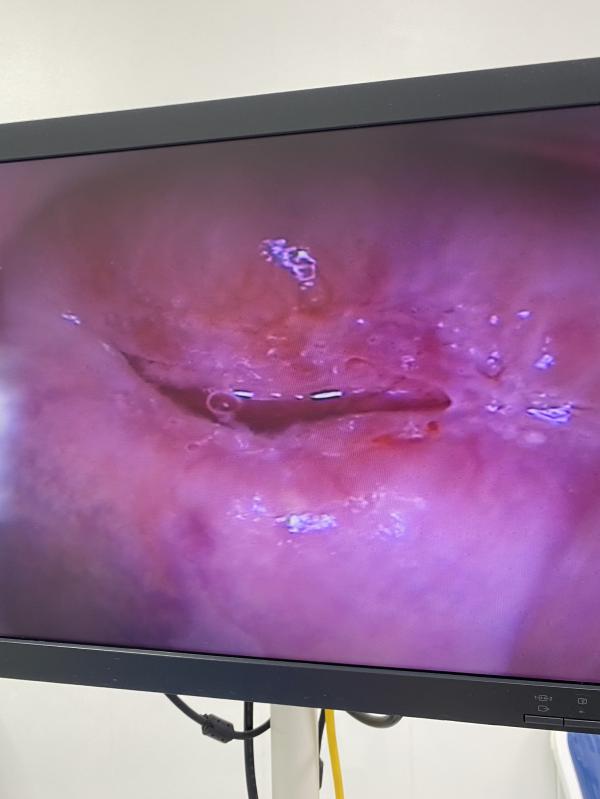

Тем более, когда предстоит сделать процедуру ( вскрытие, биопсия, эксцизия, конт. пластика , установка спирали и тд)